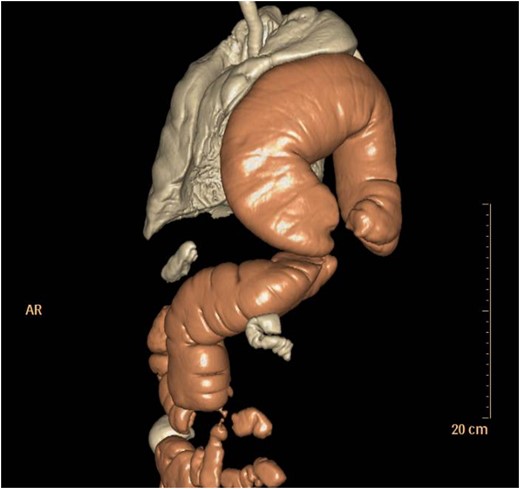

Thoraco-abdominal computed tomography (CT) showed the herniated bowel (transverse colon), translocated through a defect of about 7 cm in the left hemidiaphragm (Figs 2–4), a rightward deviation of the mediastinal structures and an atelectasis of the left lung (Fig. 5). The left colon had the appearance of a volvulus.

CT of chest showing defect on left side of the diaphragm and colon herniation in the thoracic cavity.